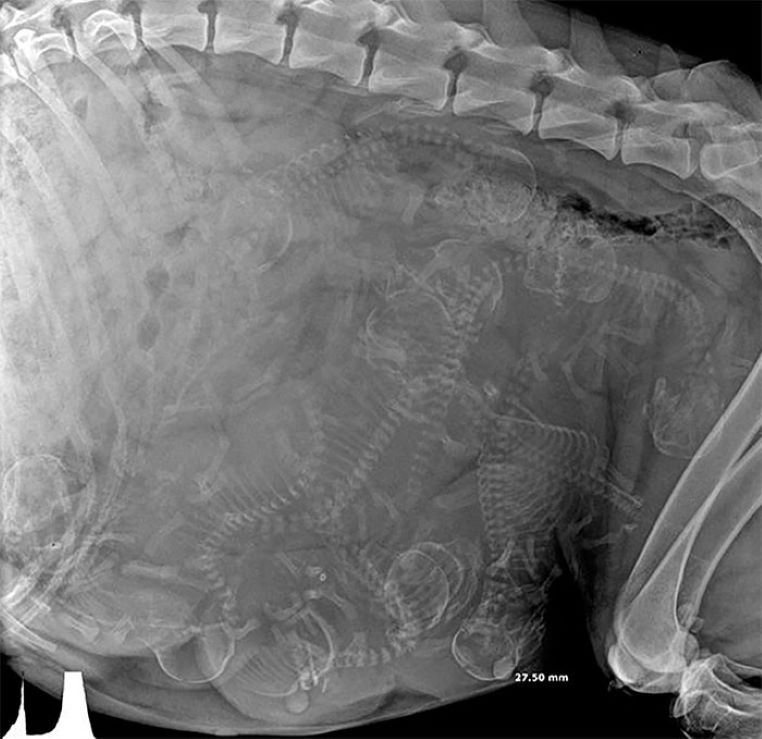

Une chienne enceinte passe sous les rayons X

galerie-rayon-x-chienne-enceinte